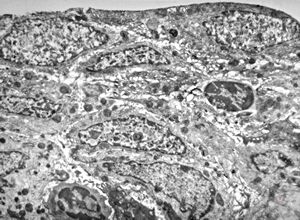

M,22y. | normal bronchial epithelium